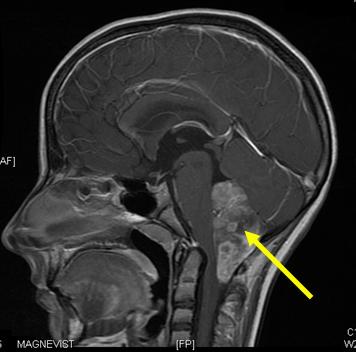

Опухоли головного мозга

Лечение рака мозга

Операция - лишь первый шаг в лечении рака мозга. Для достижения полного результата как правило, нужно облучение или иммунотерапия. Наиболее сложно поддаются лечению рецидивы опухолей мозга или метастазы. В задачу наших врачей в сложных случаях становится продление срока жизни и сохранение ее качества.